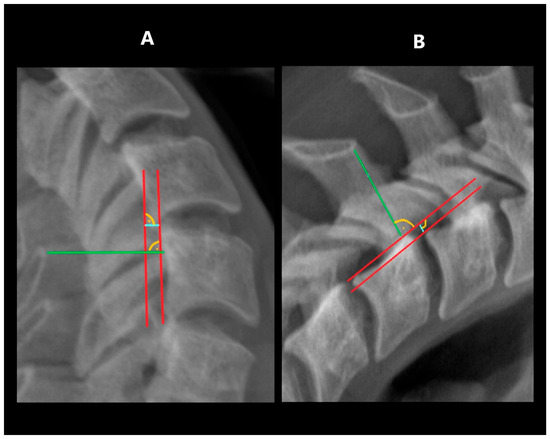

2.6. Horizontal Displacement Index (HDI)

The range of horizontal segmental mobility was measured in both functional projections. This was performed by measuring the displacement of the posterior edge of the upper vertebral body in relation to the posterior edge of the lower vertebral body. In flexion projection, the upper vertebral body should shift ventrally (forward), while in the extension projection, there should be a shift dorsally (backward). The values measured in flexion and extension were then related to the width of the spinal canal at the level of the lower vertebra. Measurements were taken at the narrowest point between the posterior contour of the vertebral body and the anterior contour of the spinous process of the same vertebra [6,12] (Figure 2).

Figure 2. Measuring HDI: (A)—in extension, (B)—in flexion. Tangent lines to the posterior edge of vertebras—red lines; horizontal displacement distance—blue lines; spinal canal width—green lines.